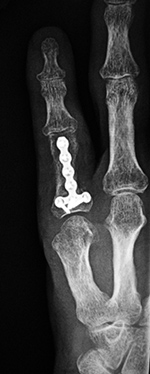

Little finger reconstruction plate

47 year-old man with fracture of the left little finger proximal phalanx.